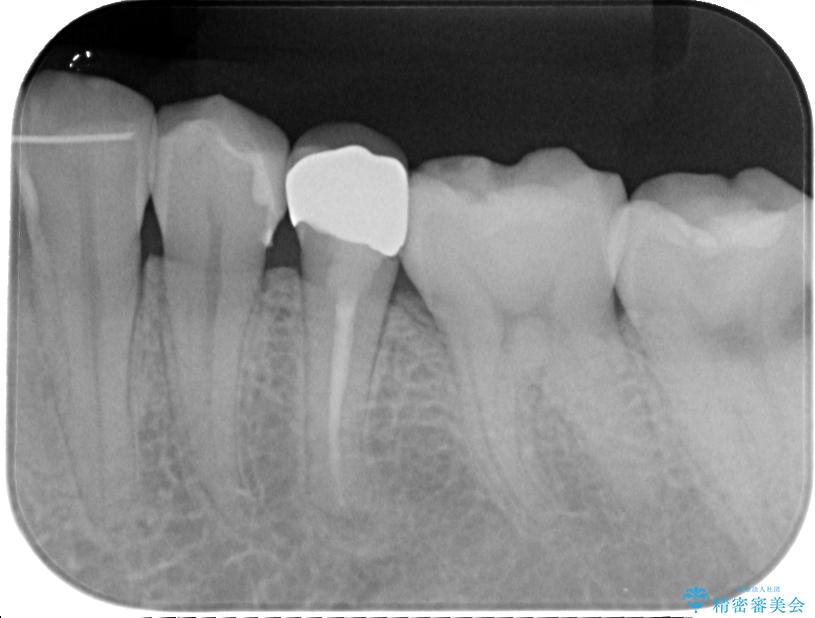

- 左下の被せものが割れたとのことで来院された患者様です。検査の結果、左下の前から4番目の歯はセラミックインレー修復、左下の5番目のところはオールセラミッククラウンによる補綴治療を行っていくことにしました。

拡大鏡視野下で被せもの、虫歯の除去を行い、オールセラミッククラウン、セラミックインレーに適した形に整えました。

患者様のご希望により左下5番目の根管治療は行っておりません。